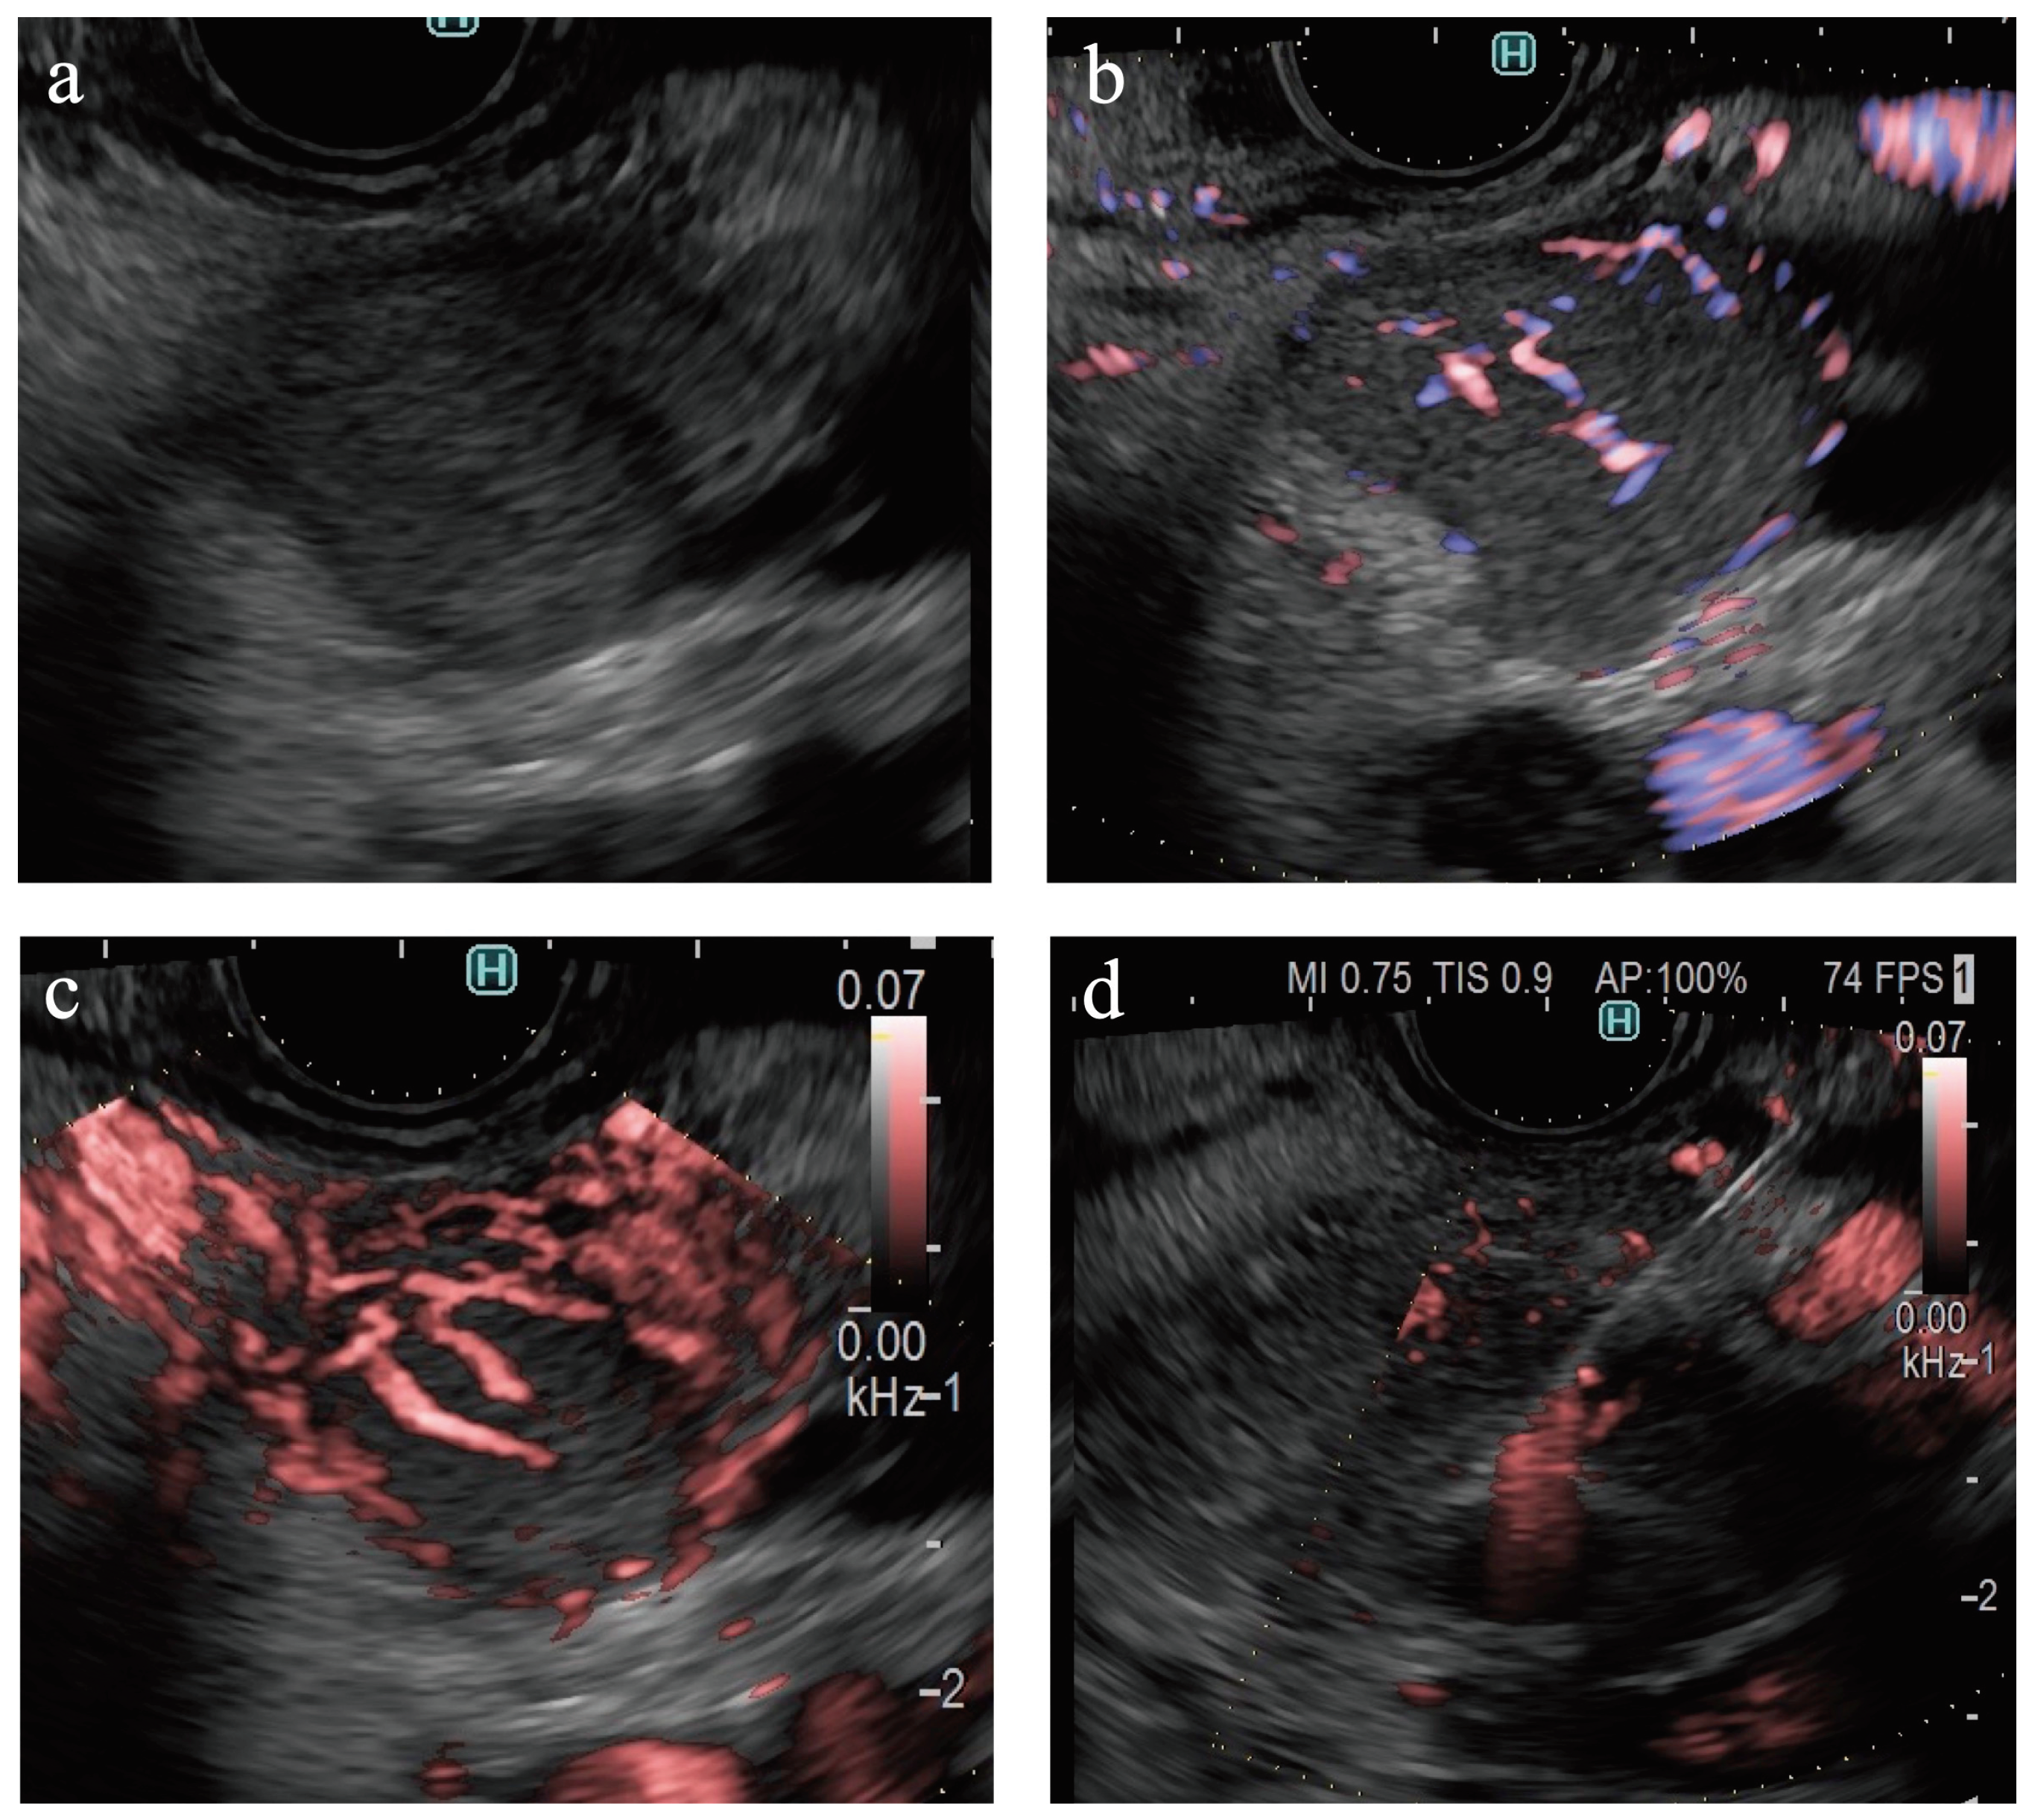

Figure 2. The diagnostic criteria for Detective Flow Imaging. (a) Vascularity was classified as hypovascular or hypervascular. (b) Vessel distribution was classified as peritumoral or intratumoral. (c) Vessel shape was classified as spotted or linear.